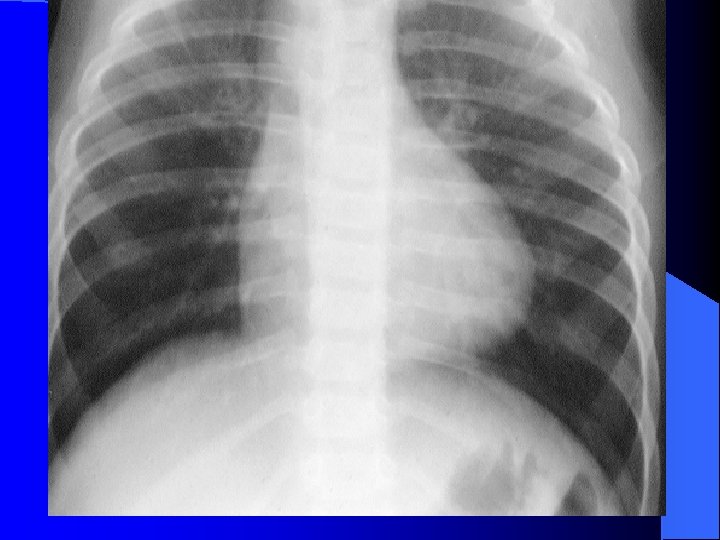

1. A 3 day old girl is found unconscious in her crib and is brought to the ED. Findings include: tachypnea, tachycardia, pallor; poor capillary refill; hepatomegaly; cardiomegaly with increased pulmonary vascular markings; hemoglobin concentration 17 gm/dl; and hematocrit, 51%. Of the following, the cardiogenic shock in this girl MOST likely is due to: l A. critical aortic stenosis l B. erythroblastosis fetalis l C. patent ductus arteriosus l D. severe hypovolemia l E. ventricular septal defect